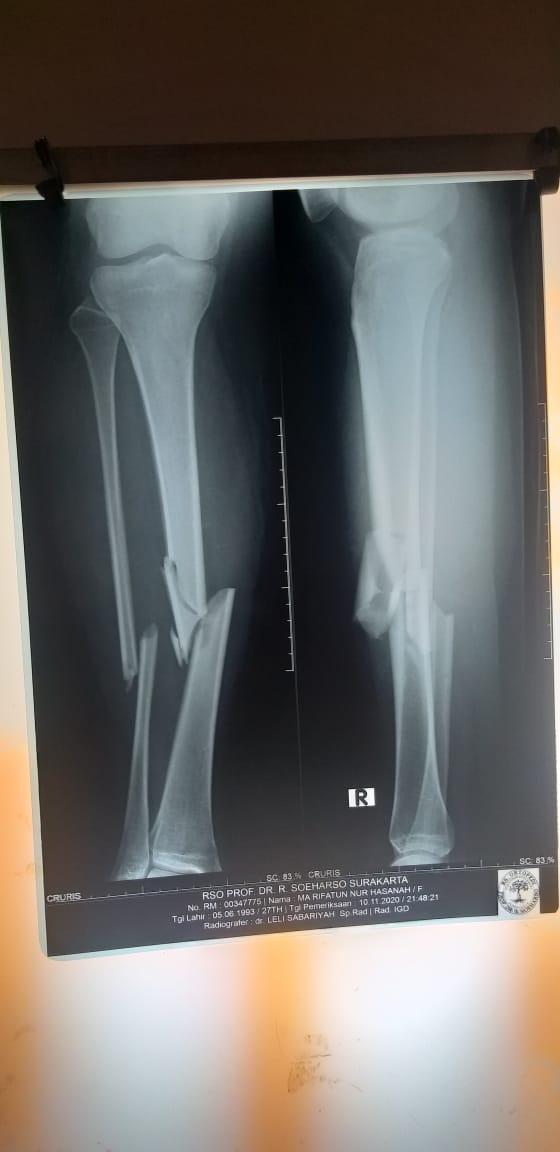

Saking kerasnya benturan sampai membuat rahang dan beberapa tulang di bagian tubuh Rifa retak, bahkan patah. Rifa langsung dibawa ke rumah sakit terdekat sambil bercucuran darah dan tubuhnya yang lumpuh sementara.

Sampai saat ini bahu dan kakinya harus masuk meja operasi, tapi sang suami kebingungan karena sudah tidak ada harta benda yang tersisa dan BPJS pun tak punya.